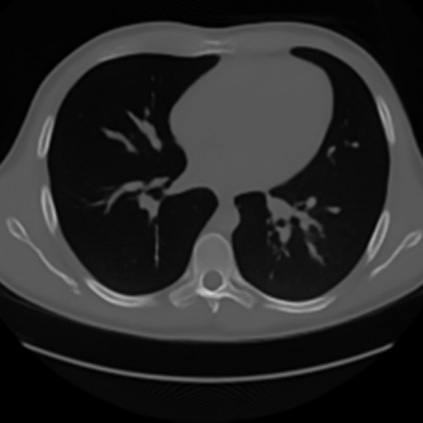

Sparse-view computed tomography (CT) -- using a small number of projections for tomographic reconstruction -- enables much lower radiation dose to patients and accelerated data acquisition. The reconstructed images, however, suffer from strong artifacts, greatly limiting their diagnostic value. Current trends for sparse-view CT turn to the raw data for better information recovery. The resultant dual-domain methods, nonetheless, suffer from secondary artifacts, especially in ultra-sparse view scenarios, and their generalization to other scanners/protocols is greatly limited. A crucial question arises: have the image post-processing methods reached the limit? Our answer is not yet. In this paper, we stick to image post-processing methods due to great flexibility and propose global representation (GloRe) distillation framework for sparse-view CT, termed GloReDi. First, we propose to learn GloRe with Fourier convolution, so each element in GloRe has an image-wide receptive field. Second, unlike methods that only use the full-view images for supervision, we propose to distill GloRe from intermediate-view reconstructed images that are readily available but not explored in previous literature. The success of GloRe distillation is attributed to two key components: representation directional distillation to align the GloRe directions, and band-pass-specific contrastive distillation to gain clinically important details. Extensive experiments demonstrate the superiority of the proposed GloReDi over the state-of-the-art methods, including dual-domain ones. The source code is available at https://github.com/longzilicart/GloReDi.